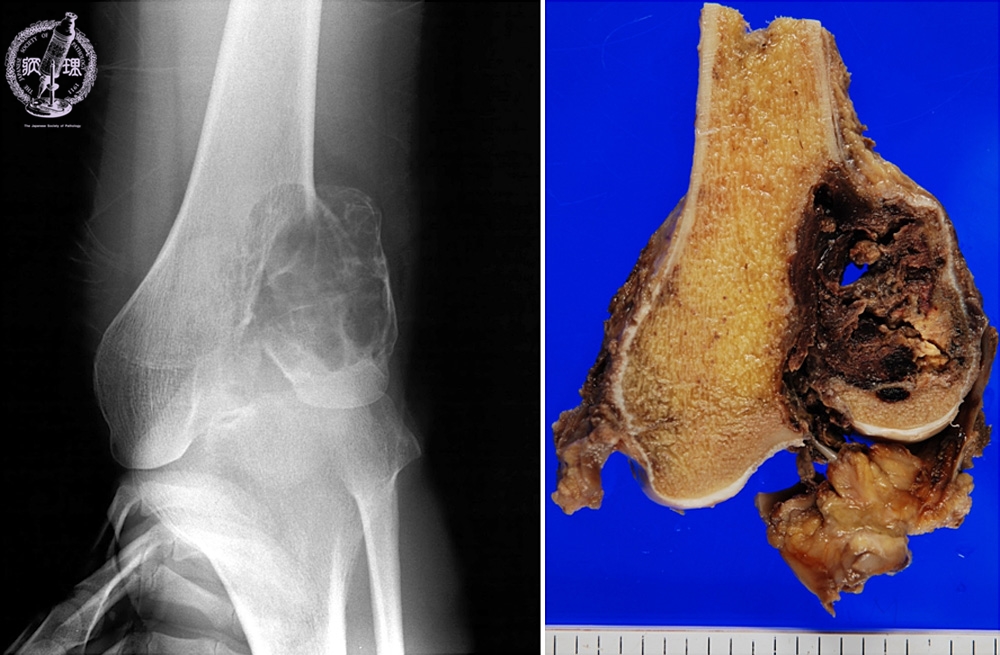

X-ray findings (Left) and macroscopic view (Right): X-ray shows bubbly shadow at the epiphysis. Macroscopic finding is concordant, showing circumscribed, hemorrhagic lesion.